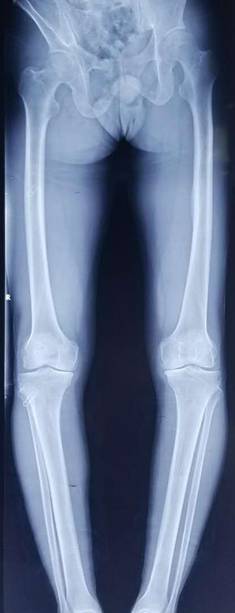

手术技术上与国内领先医院接轨,并不断创新。系统开展膝关节骨性关节炎的阶梯治疗方案,早期采用中医中药、理疗、肌力训练等方法;中期采用膝关节周围截骨、单髁置换等手术治疗,充分保留膝关节功能,术后患者康复快。终末期采用膝关节表面置换术治疗。系统开展股骨头无菌性坏死的保头治疗,早期可采用中医中药内服,钻孔减压术治疗,中期可采用髋关节外科脱位技术,充分刮除头内坏死骨,植入新鲜骨质,使坏死股骨头重新获得新生。常规开展复杂的人工髋膝关节置换手术、人工髋膝关节翻修手术。术后采用先进的康复理念和康复方案帮助患者在无痛状态下恢复关节功能。

全膝关节表面置换术治疗重度骨性关节炎、全髋关节置换术治疗晚期股骨头坏死、先天性髋关节发育不良、股骨颈骨折。微创钻孔减压、腓骨移植、髋关节外科脱位大转子截骨技术治疗股骨头坏死。直接前路微创髋关节置换术。膝关节周围截骨术、单髁置换术阶梯治疗膝关节骨性关节炎。人工反置式肩关节置换术治疗巨大肩袖损伤;关节镜下微创肩袖撕裂修补术,肩峰下减压术及肩关节脱位的手术。髋膝关节置换术后翻修术。

全膝表面置换术治疗重度骨关节病

优点:疗效可靠,膝关节病的最终解决方案。